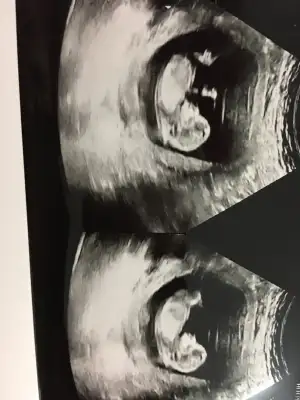

Kızlarrrr cinsiyet tahminlerinizi alıyımm:KK200:

Eklentiler

• image.webp

image.webp

37,2 KB · Görüntüleme: 102